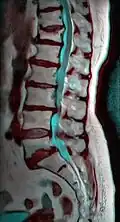

MRI of L5-S1 anterolisthesis -